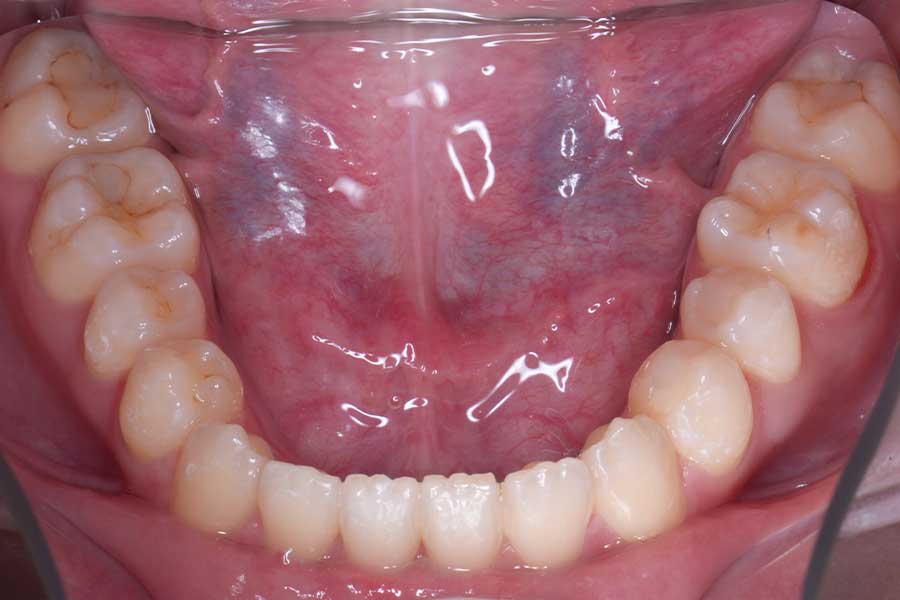

治療後

主訴 前歯で咬み切れるようになりたい

治療内容 ハーフリンガル矯正(上顎裏側・下顎表側矯正)